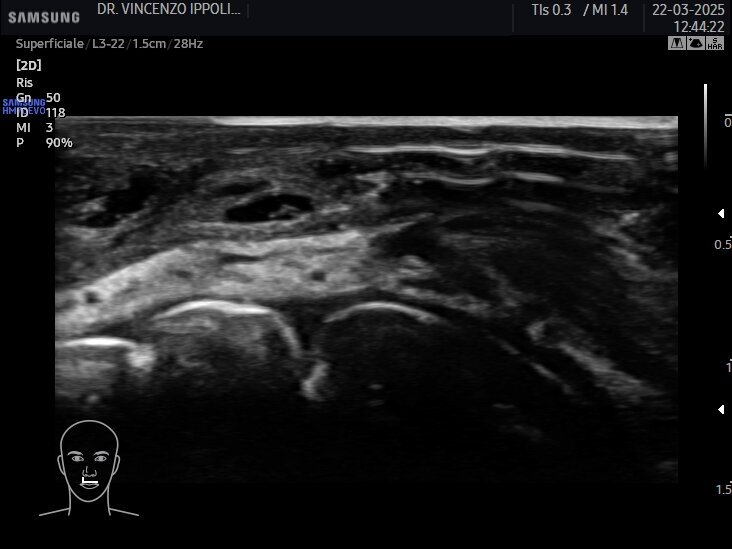

Gli ultrasuoni forniscono immagini in tempo reale con accuratezza variabile e dipendente dalle capacità dell’operatore e dalle potenzialità dell’apparecchiatura ecografica per uno studio accurato della cute e degli strati più superficiali del volto ma nascosti dall’epidermide (Fig. 1). Consentono una mappatura precisa delle strutture vascolari a prescindere dalle loro varianti anatomiche ed una valutazione della motilità dei piani muscolari. Ciò significa che con l’esame ecografico è possibile passare dall’osservazione anatomica statica a quella dinamica e valutare le straordinarie differenze ai fini diagnostici, esecutivi e post-operatori (Fig. 2) (clicca QUI e guarda il video). A causa della crescente popolarità delle procedure estetiche mininvasive al volto mediante tecniche iniettive/infiltrative/implantari, l’esame ecografico facciale è diventato fondamentale per tracciare i prodotti iniettabili, prevenire complicanze e, se necessario, riconoscerle per intervenire tempestivamente. Eventi avversi possono verificarsi al momento dell’iniezione, come le occlusioni o le compressioni vascolari, subito dopo il trattamento, come le infezioni, o diversi mesi dopo, come la comparsa di reazioni nodulari infiammatorie. Eseguire una metodica estetica al volto, sia essa infiltrazione di filler, iniezione intramuscolare di tossina botulinica o impianto di fili di trazione o di biostimolazione, sotto guida ecografica, fornisce un riscontro dinamico contestuale del posizionamento del riempitivo, consentendo al clinico di operare nell’area anatomica prescelta evitando sconfinamenti indesiderati (clicca QUI e guarda il video).

L’incidenza di complicanze vascolari dopo le iniezioni di filler pare essere 1/6600 (0,015%). Tuttavia, sebbene questo rischio non sembri molto elevato, anche un operatore esperto può incorrere in questo evento avverso. Se, da un lato, gli ultrasuoni possono aiutare nell’identificare e valutare il decorso dei vasi sanguigni a rischio di occlusione o compressione (Fig. 3), dall’altro, in caso di evento avverso correlato al filler a base di acido ialuronico, l’enzima ialuronidasi può essere iniettato con la guida degli ultrasuoni esattamente nel deposito del prodotto per una sua mirata dissoluzione (Fig. 4). Con l’avanzare dell’età, l’immagine della cute si modifica sia negli spessori sia nel numero degli annessi. L’esame ecografico contribuisce a visualizzare il progressivo deterioramento cutaneo: un assottigliamento del derma, la riduzione delle fibre collagene, la degenerazione delle fibre di elastina e la disidratazione influiscono sull’ecogenicità dei tessuti esaminati (Fig. 5).

Esame ecografico: quando Gli ultrasuoni – per mezzo dell’esame ecografico - sono usati in tutta le specialità della medicina come strumento diagnostico: non nocivo, indolore, affidabile e relativamente poco costoso, possono davvero agevolare l’Odontoiatra che intende esercitare la medicina estetica nel proprio studio professionale evidenziando inequivocabilmente l’anatomia degli spazi e delle strutture del volto, lo spessore dei tessuti molli, le immagini delle patologie che eventualmente si sovrappongono sul viso, la posizione dei vasi e l’andamento del flusso ematico nei vasi, la presenza di rami “importanti” del nervo faciale.

In più gli ultrasuoni possono valutare lo stato del filler – puro o prodotto in composti con altre sostanze – infiltrato al momento o in precedenza e guidare e seguire nel tempo procedure iniettive dell’anatossina botulinica, dei filler a base di acido ialuronico e l’impianto dei fili di trazione e di idratazione. Gli ultrasuoni sono davvero utili nel follow up dei pazienti, nella correzione dei casi clinici insoddisfacenti, nella gestione degli eventi avversi fra cui le complicanze (Fig. 6).

Accanto a immagini statiche di sicuro aiuto per i professionisti esperti della metodica, le immagini dinamiche rilevate nel corso delle procedure infiltrative per i filler, iniettive nel caso della tossina botulinica e implantari nel caso dell’impianto di fili di biostimolazione/idratazione e di fili di trazione/sospensione risultano assolutamente dirimenti sul giudizio di wellpractice o malpractice (clicca QUI e guarda il video). La differenza fra immagini statiche ed immagini dinamiche consiste proprio nella possibilità inopinabile di valutare nel corso della disamina dei filmati relativi all’esame ecografico rilevato simultaneamente all’iniezione, all’infiltrazione, all’impianto di tossina botulinica, di filler, di fili, se queste procedure sono state correttamente eseguite nelle varie fasi operative o viceversa.

Nel particolare l’esame ultrasonico registrato nei momenti in cui sono eseguite le procedure medicoestetiche – vero e proprio occhio di ciò che avviene al disotto della barriera cutanea – permette di rilevare senza dubbio alcuno:

l’adeguato spessore dei tessuti oggetto di trattamento e pertanto la giustificazione anatomica della proposta terapeutica dell’operatore (Fig. 1);

la struttura anatomica che accoglie il farmaco o il dispositivo medico;

la mappatura dei vasi della zona oggetto di intervento (Fig. 7 - clicca QUI e guarda il video; Fig. 8 - clicca QUI e guarda il video; Fig. 9 - clicca QUI e guarda il video);

la posizione della sonda che ha rilevato l’esame (body marker) (Fig. 10);

il risultato finale (Fig. 11).